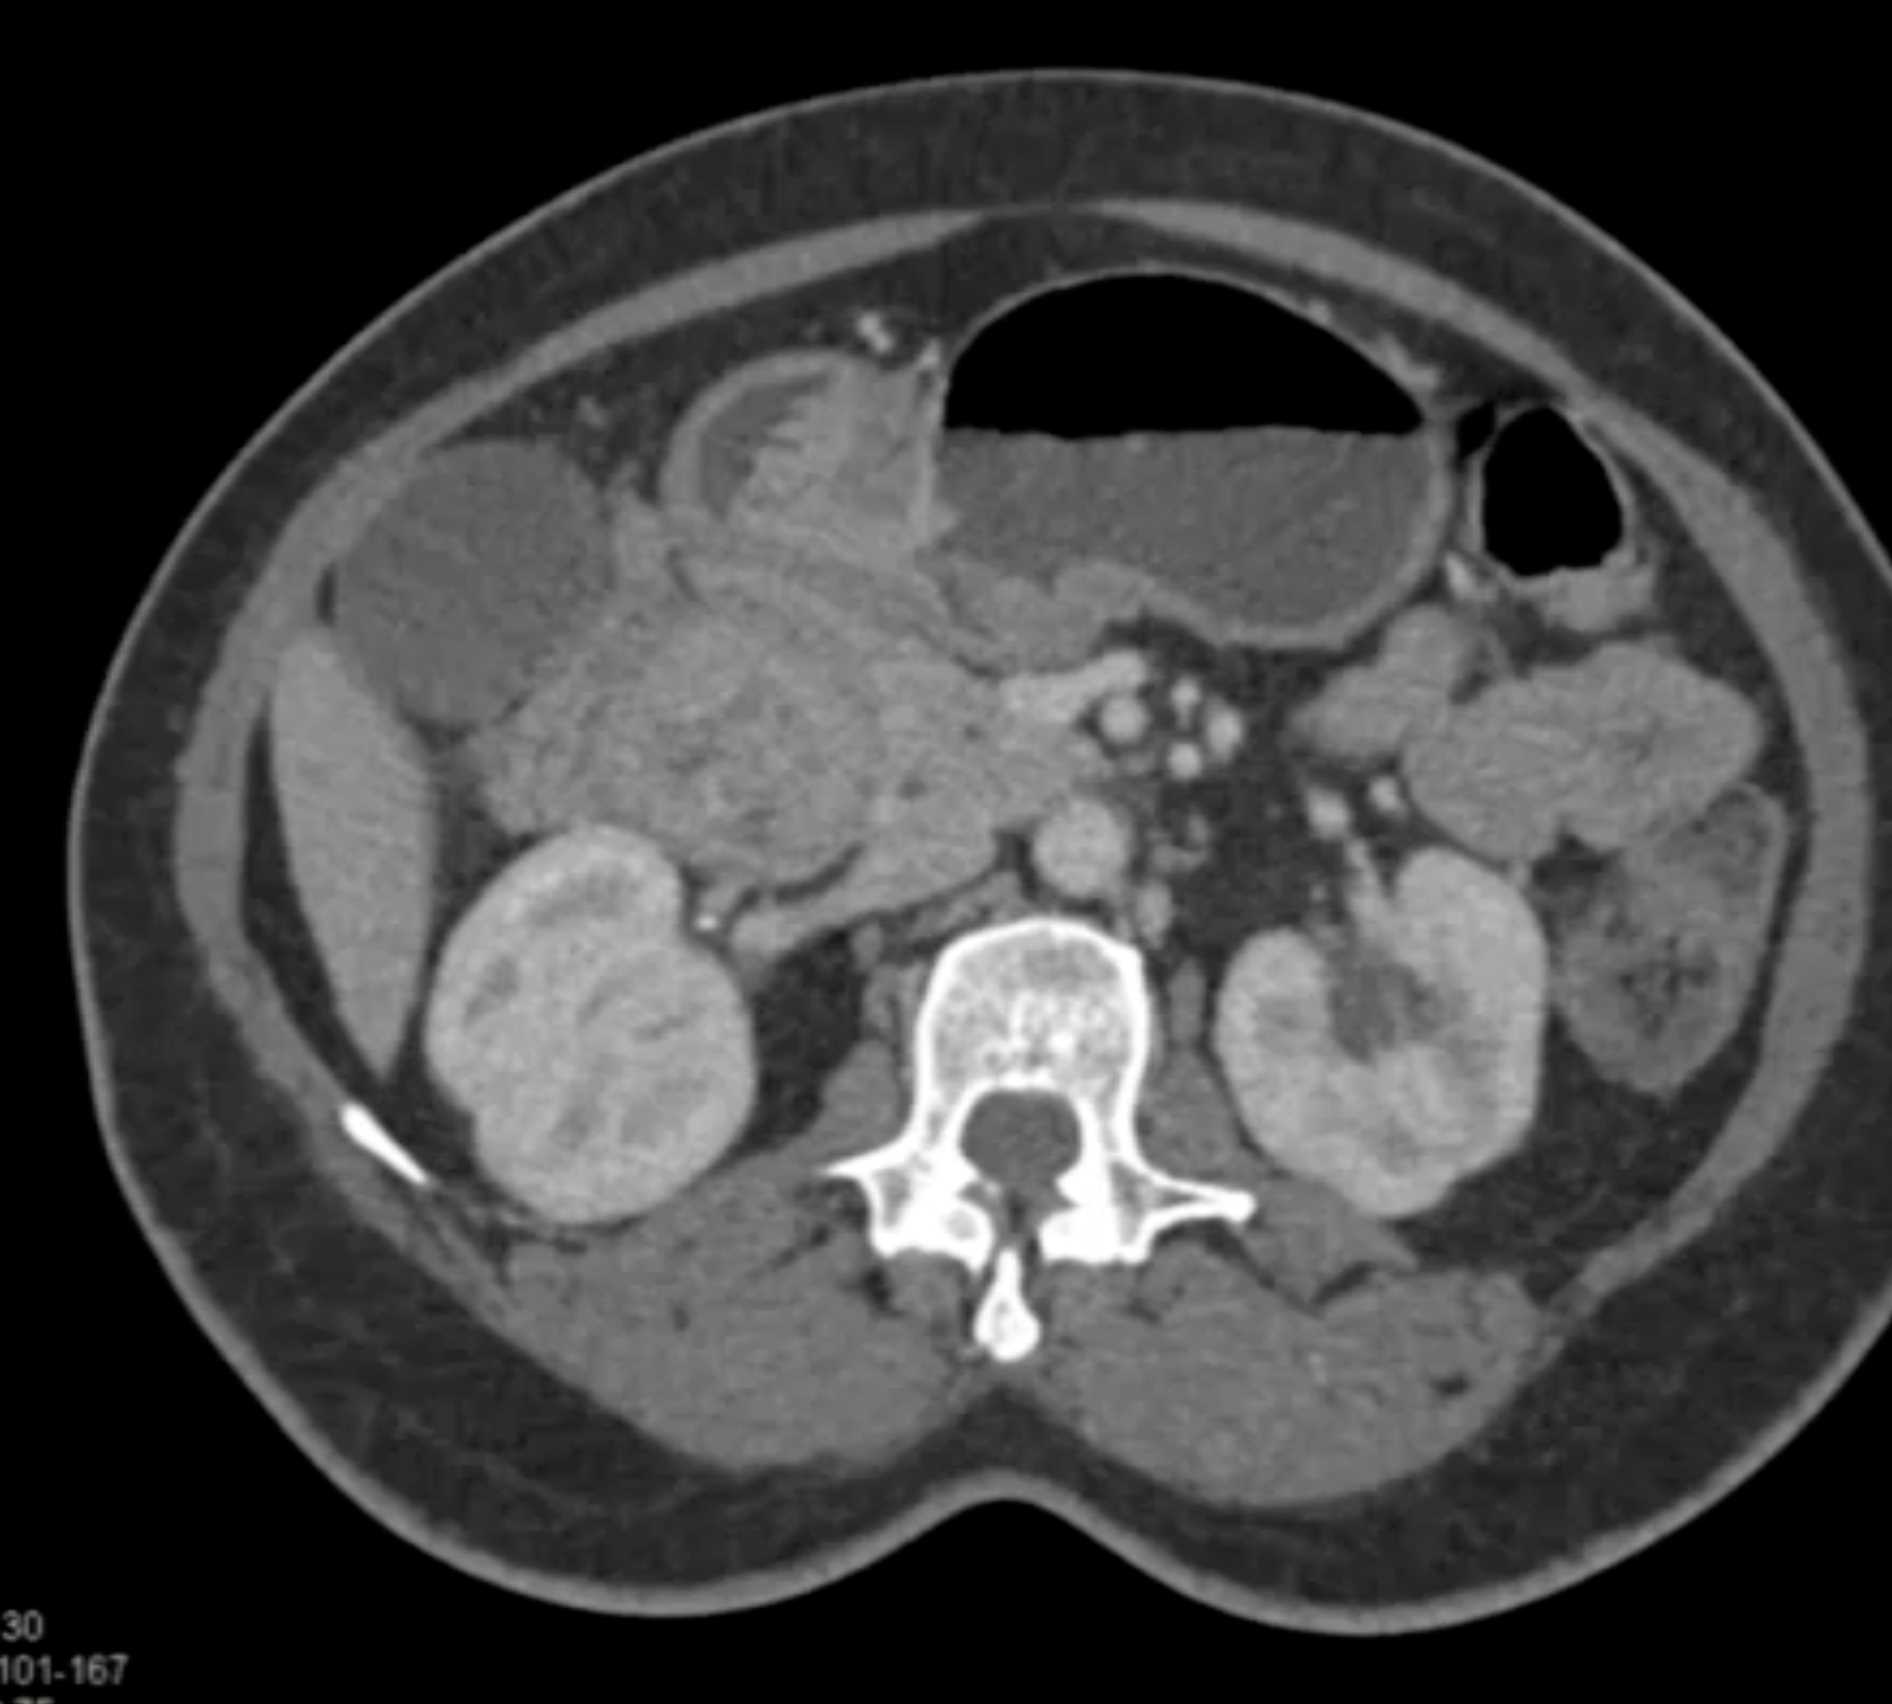

Lagre Gastric GIST Tumor